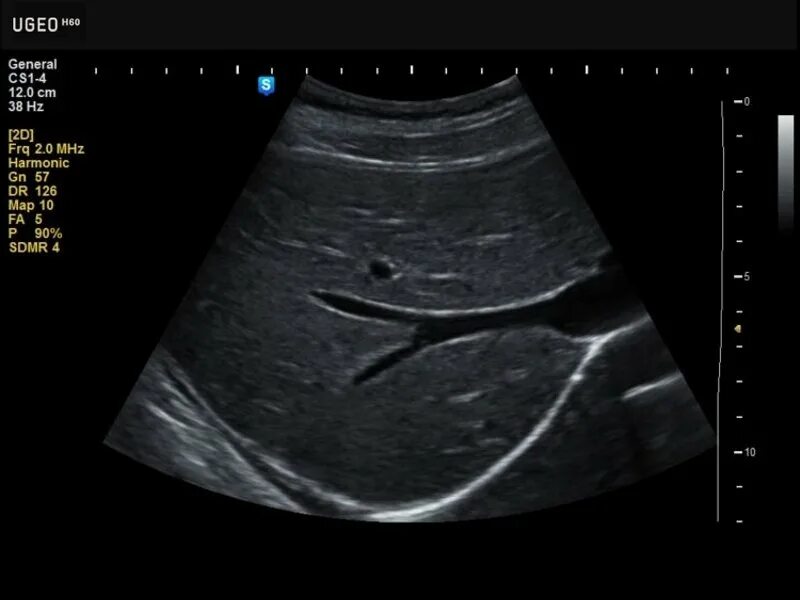

Режимы узи аппарата